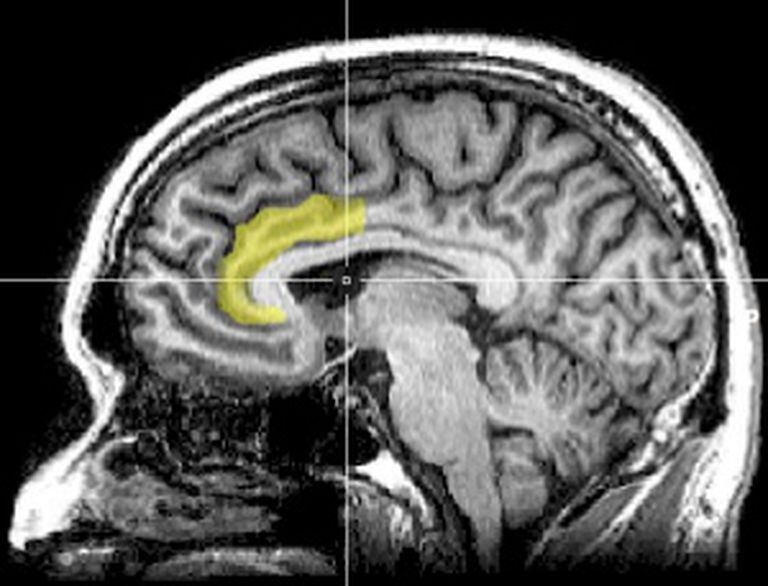

Em 2007, uma equipe de pesquisadores das universidades de Nova York e Califórnia realizou um trabalho experimental, publicado na prestigiosa revista Nature Neuroscience. O grupo mostrou, através de potenciais elétricos evocados e imagens de ressonância magnética funcional, que em situações de conflito as pessoas politicamente liberais apresentam mais atividade que as politicamente conservadoras na circunvolução cingulada anterior, uma região do lobo temporal do cérebro e responsável, entre outras funções, por responder, feito um alarme biológico, a situações onde o que raciocinamos não coincide com o que sentimos.

Desse modo, os pesquisadores concluíram que, frente às situações novas que requerem modificação dos comportamentos habituais, os liberais têm mais sensibilidade neurocognitiva que os conservadores. Também deduziram que a menor sensibilidade neurocognitiva dos conservadores em tais situações poderia explicar seu comportamento mais sistemático e persistente. A avaliação neurofisiológica desse estudo foi tão consistente que serviu para prever com bastante exatidão se os participantes tinham votado em John Kerry ou George Bush na eleição de 2004 nos Estados Unidos. Detalhe importante: ao falar de sensibilidade neurocognitiva, os autores do trabalho não se referem a um tipo de sensibilidade moral, e sim a um modo fisiológico de funcionamento do cérebro.

Posteriormente, em 2011, um estudo de pesquisadores do University College de Londres, também com imagens neurológicas de ressonância magnética, mostrou que os liberais tinham um volume maior de massa cinzenta, ou seja, de neurônios, nessa região cerebral, a circunvolução cingulada anterior, enquanto que os conservadores superavam os liberais no volume dessa mesma substância na amígdala, uma estrutura do cérebro emocional. No entanto, ainda é preciso determinar se essas diferenças cerebrais são ou não as causadoras das orientações políticas das pessoas.